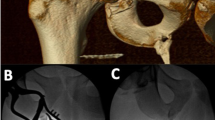

Heterotopic ossification (HO) is characterized by the abnormal formation of bone in soft tissues where bone typically does not form, which can be induced by multiple factors, and nerve injury is commonly considered the predominant factor [1,2,3]. Approximately 10% to 53% of HO patients suffer from postcentral nervous system injury [2]. Injuries to the spinal cord or peripheral nerves can also lead to HO [3, 4]. HO is most commonly observed in the hip joint in patients with spinal cord injury, but within patients with traumatic brain injury, HO may occur throughout the body such as in the shoulder and knee joints [2]. However, the structure and characteristics of HO induced by different forms of trauma exhibit significant similarities. The cellular origins of HO formation are relatively complex [5]. Cells involved in pathological ossification may originate from the osteogenic differentiation of various stem cells under specific stimuli [6]. The formation of cartilage occurs first followed by cartilage ossification in traumatic HO. In addition, some mesenchymal stem cells (MSCs) at the site of traumatic HO injury accompanied by nerve damage can also affect cartilage ossification and the differentiation into osteoblasts.